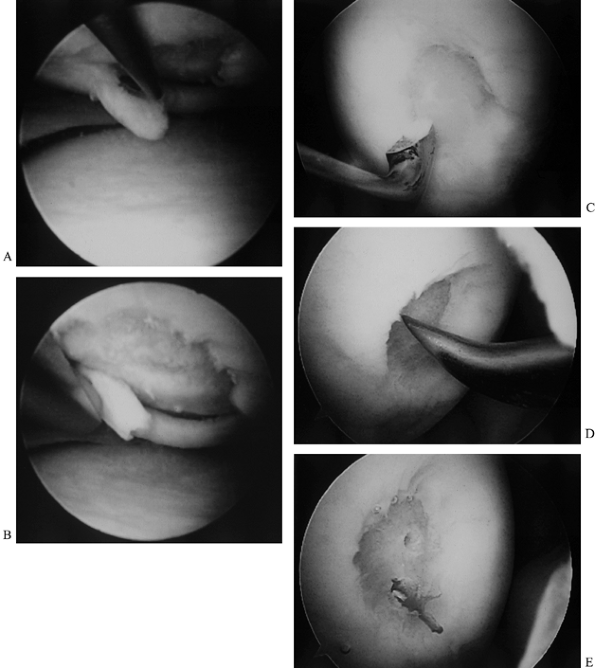

(24,34). This in turn stimulates a tissue healing response (Fig. 86.3; see also COLOR FIG. 86.3).

![]() |

Figure 86.3. (See COLOR FIG. 86.3.) Technique for debridement, abrasion arthroplasty, and microfracture. A: Arthroscopic view shows a chondral flap tear on the medial femoral condyle. B:

The unstable flap and unstable edges of the cartilage are debrided. Note that this is a full-thickness defect exposing underlying subchondral bone. C: The debridement is completed by smoothing the edges with a curet. D: An awl is used to punch through (microfracture) the subchondral bone to bring cells into the defect. E: Two microfracture holes, with bleeding from one. |